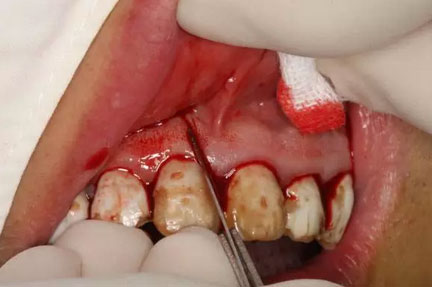

圖8.垂直切口+齦溝內(nèi)水平切口,水平切口延至23遠(yuǎn)中乳頭。

圖9.切口的交界處翻瓣,注意翻全厚瓣。

圖10.翻開粘膜瓣發(fā)現(xiàn)有唇側(cè)部分骨壁不規(guī)則缺損。